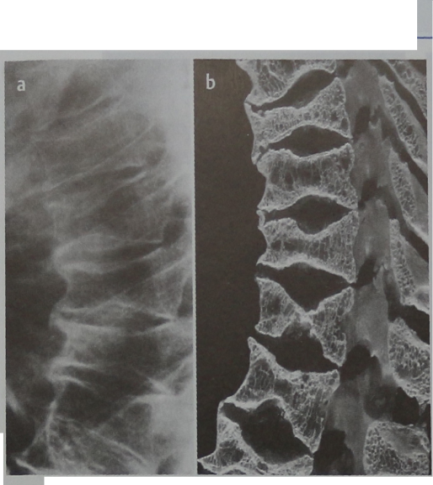

Рентгеновские снимки и медицинские изображения компрессионных переломов